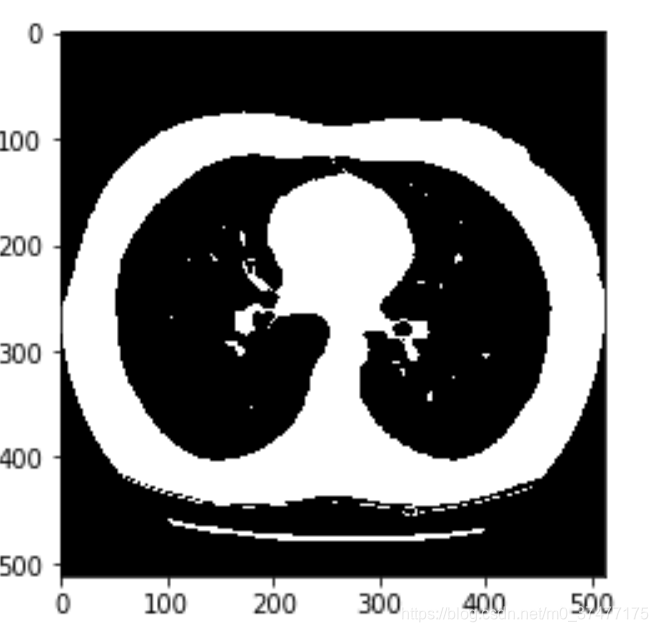

显示下肺窗下的图像:

img_norm_arr = sitk.GetArrayFromImage(img_norm)

plt.imshow(img_norm_arr[68], cmap='bone')

使用区域生长法分割:

seed_pts = [(108, 246, 68), (390, 255, 68)]

img_grow_Confidence = sitk.ConfidenceConnected(img, seedList=seed_pts,

numberOfIterations=0,

multiplier=2,

initialNeighborhoodRadius=1,

replaceValue=1)

打印结果:

img_grow_arr_Confidence = sitk.GetArrayFromImage(img_grow_Confidence)

plt.imshow(img_grow_arr_Confidence[68])

结果上有很多的空洞需要填补。